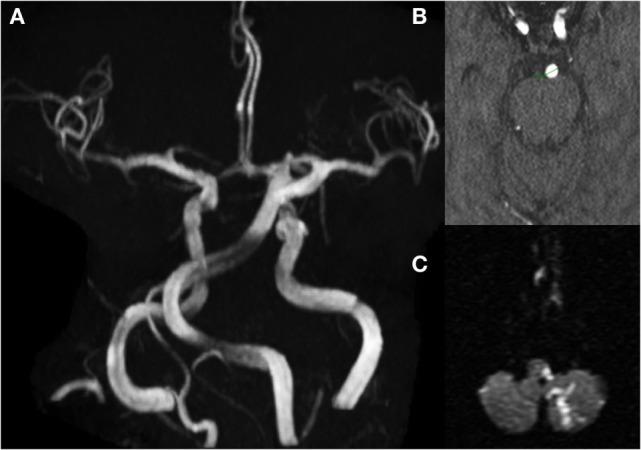

颅内动脉迂曲扩张症

Intracranial Arterial Dolichoectasia.

An increased diameter (ectasis) and/or long and tortuous course (dolichosis) of at least one cerebral artery define intracranial arterial dolichoectasia (IADE). IADE could be detected incidentally or may give rise to an array of neurological complications including ischemic stroke, intracranial hemorrhage, or compression of surrounding neural structures. The basilar artery is preferentially affected and has been studied in more detail, mainly due to the presence of accepted diagnostic criteria proposed by Smoker and colleagues in 1986 (1). Criteria for the diagnoses of dolichoectasia in other cerebral arteries have been suggested. However, they lack validation across studies. The prevalence of IADE is approximately 0.08-6.5% in the general population, while in patients with stroke, the prevalence ranges from 3 to 17%. Variations among case series depend on the characteristics of the studied population, diagnostic tests used, and diagnostic criteria applied. In rare instances, an underlying hereditary condition, connective tissue disorder, or infection predispose to the development of IADE. However, most cases are sporadic and associated with traditional vascular risk factors including advanced age, male gender, and arterial hypertension. The link between this dilative arteriopathy and other vascular abnormalities, such as abdominal aortic aneurysm, coronary artery ectasia, and cerebral small vessel disease, suggests the underlying diffuse vascular process. Further understanding is needed on the physiopathology of IADE and how to prevent its progression and clinical complications.

摘要